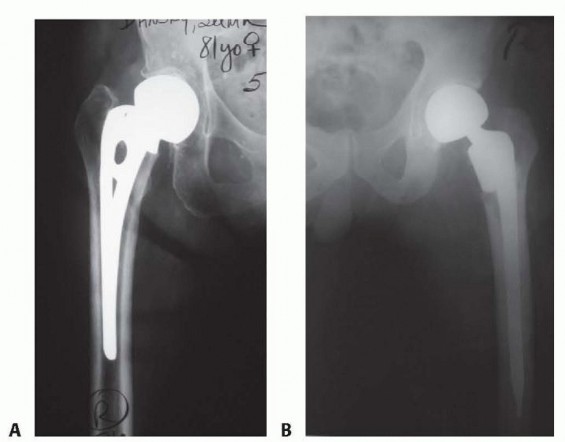

Clinical & Radiographic Imaging Archive